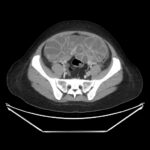

Ovarian hyperstimulation syndrome (OHSS) is a potentially life-threatening complication of assisted reproductive technology (ART). Here, we present the case report of a 30-year-old female undergoing infertility treatment who presented to the emergency department (ED) with nausea and vomiting, abdominal distention, and shortness of breath. On physical exam, she had notable ascites. Computed tomography (CT) of the abdomen and pelvis and pelvic ultrasound (US) revealed significant ascites and enlarged ovaries with multiple cysts. She was diagnosed with severe OHSS and admitted to obstetrics and gynecology (OBGYN) service for five days where she underwent intravenous (IV) hydration and paracentesis. This case report reviews the clinical presentation, categorization, management, and prevention of OHSS and provides examples of imaging findings consistent with the condition.